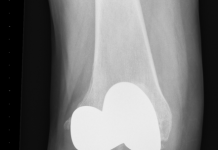

Voor een armklikprothese zijn drie operaties nodig. Tijdens de eerste operatie brengt de chirurg een metalen pin aan in de mergholte van het bot. De buitenkant van deze pin heeft een ruw oppervlak. Deze ruwe kant wordt door het bestaande bot herkend en geaccepteerd, waardoor de pin maximaal kan ingroeien en verankeren. Zes tot acht weken hierna vindt de tweede (kortdurende) ingreep plaats. De chirurg maakt een gaatje in de huid en schroeft een verbindingspin in de eerder aangebrachte pin. Deze verbindingspin steekt een stukje naar buiten zodat de prothese hieraan vastgeklikt kan worden.

21 oktober 2013: Operatie 1 door chirurg Jan Paul Frölke: de metalen pin wordt in het bot gebracht.

13 januari 2014: Operatie 2 door chirurg Jan Paul Frölke: de verbindingspin wordt aan de eerste pin vastgemaakt.